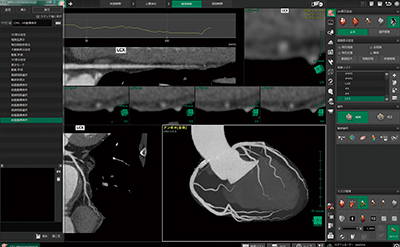

画像のノイズ成分,狭窄病変における画素値の不連続性などの影響を受けない高精度なセグメンテーションを行えるため,短時間で処理でき,かつユーザー間において画像作成結果の差異を生じない画像を提供できる(図1)。

図1 CT,MR画像から自動で心臓,冠動脈を抽出した画像例

a:RCA #1 Subtotal Occlusion。高度狭窄を有する冠動脈CT画像。

b:LAD #6 Stenosis。狭窄を有する冠動脈MR画像。